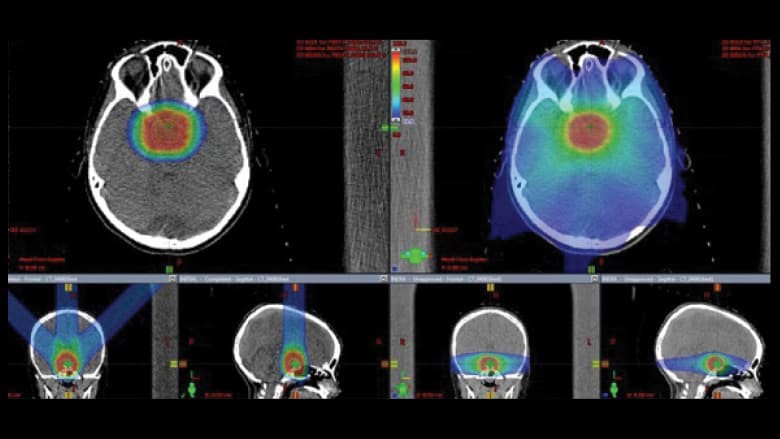

颅咽管瘤在大脑区域发展,周围有许多关键结构,包括视觉通路、垂体、下丘脑、颞叶、脑干和主要的脑血管。这种复杂的颅内环境对放射剂量的传递提出了挑战,并具有的放射诱导毒性的风险。与基于光子的放射疗法相比,质子疗法可以减少对靶点周围未受累组织的放射剂量。质子疗法治疗颅咽管瘤的疗效报告与光子疗法相当,但急性作用很小,后期的副作用也大幅减少。颅咽神经瘤囊性成分的不确定性给放射肿瘤学家带来了又一个挑战。

放射疗法在局部切除或无法切除的颅咽管瘤中起着重要的作用。当前的化疗方案无法治愈。接受现代放射剂量治疗的颅咽管瘤患者预后良好,通常可以长期生存。颅咽管瘤常见于儿科人群,发病年龄在5至14岁之间。因此,放射治疗的后期效果可能会长期性地影响其功能和生活质量,这是一个高度相关的生存问题。

放射疗法也导致这些区域的功能障碍,部分或完全丧失视力或血管病导致中风可导致终身损害。垂体和下丘脑功能的部分或完全丧失可导致终身补充药物。颞叶和海马的偶然照射后,记忆力,处理速度和智商(IQ)可能会长期降低,患者越年轻遭受的损害越大。

质子治疗适合接近处于风险中的串行器官的癌症,包括脊索瘤、鼻咽癌、鼻旁鼻窦癌和颅咽管瘤等颅内肿瘤。另一方面,质子治疗也可以使处于风险中的平行器官附近的癌症受益,因为处于风险中的平行器官对辐照量敏感,通过质子治疗可以大大降低辐射量。

INC国际神经外科提示,对于颅咽管瘤的放疗,质子治疗是较好的新选择,不建议做伽马刀治疗,因为颅咽管瘤的生长方式(即外形)不规则,伽马刀的准确放射点很难覆盖全部肿瘤边界,可造成放射点的盲区,此盲区内的肿瘤没有接受到放射线。一般4岁以上的儿童都可接受放疗,质子放疗以其顺利性、副作用低、对脑组织损害小而著称,适用于老人、儿童群体。